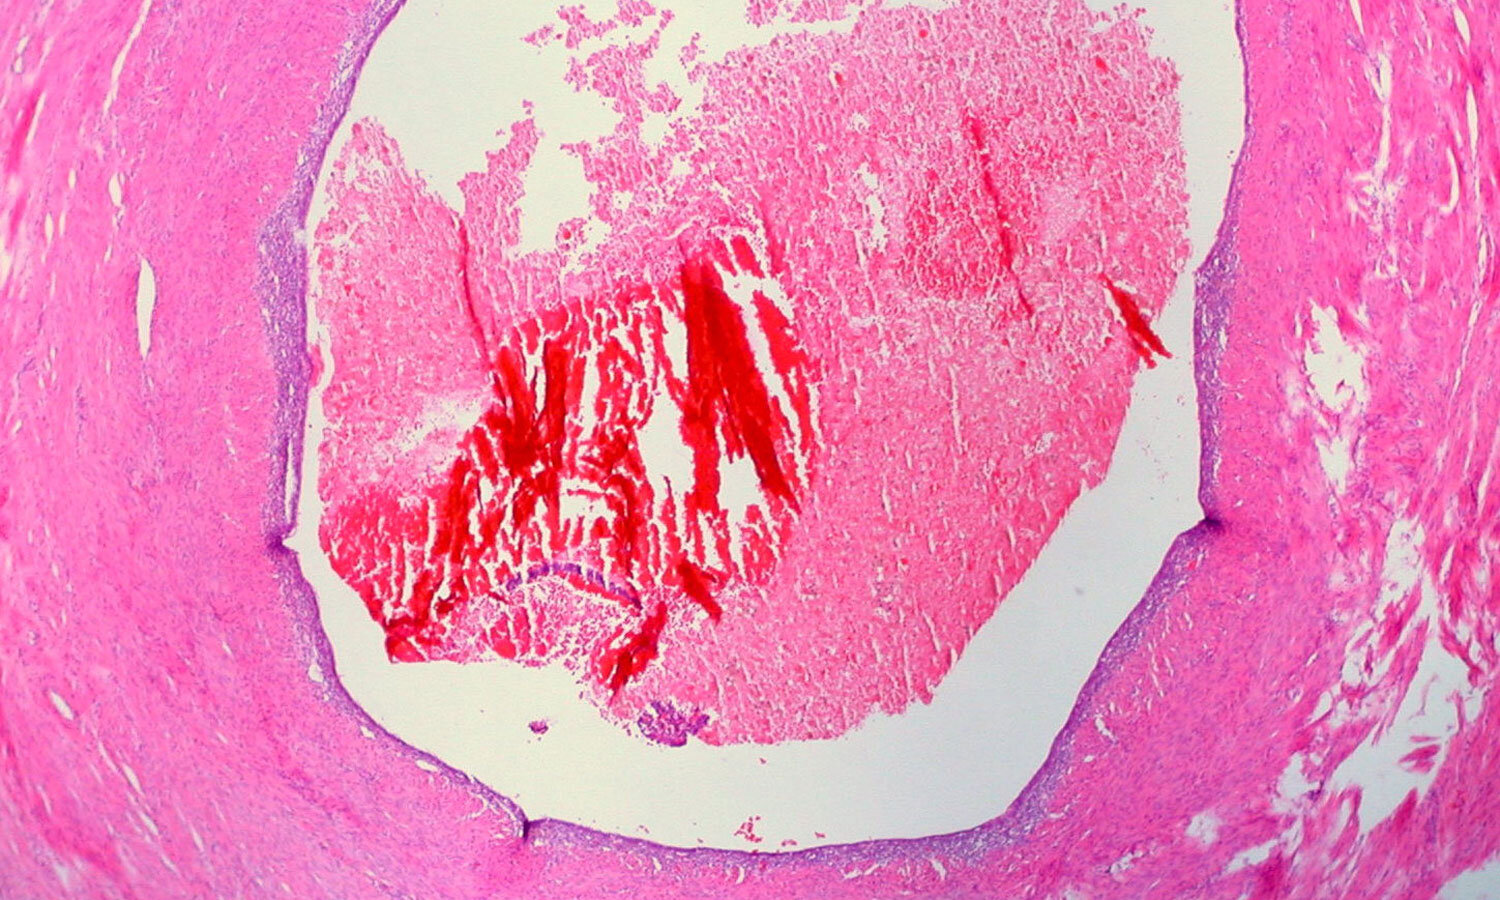

Endometriosis is a painful condition in which the inner lining of the uterus—the endometrium—starts colonizing its neighbors in the pelvic cavity. The endometrium is the thing that thickens, breaks down, and then bleeds out every month. So having endometriosis is like having multiple periods—not just from your womb, but from a bunch of other parts on your insides. (I don’t even have a period, but I’m getting crampy and bloated just thinking about this.)

The most common target is the ovaries, but endometriosis can affect the peritoneum, bladder, intestines—any of that viscera stuff.